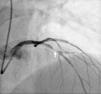

Caso clínicoTrata‐se de um indivíduo do sexo masculino de 41 anos, com antecedentes de hipertensão arterial, tabagismo (20 unidades maço ano) e dislipidemia (análises prévias com LDL 107mg/dL), sem história familiar de DC, que apresentou como primeira manifestação de DC um EAMSSST a 4 de março de 2016. Realizou cateterismo cardíaco cerca de 12h após admissão, no qual se revelou a presença de DC envolvendo, de forma extensa, vários segmentos do território da artéria circunflexa (Cx), com estenose ostial de 50% a que se associa uma lesão de 70‐90% na bifurcação para a saída da primeira obtusa marginal (OM1), e ainda uma lesão de 70‐90% num ramo intermediário. No território da artéria descendente anterior (DA) era visível uma lesão discreta, com redução do lúmen inferior a 30% (Figura 1). No mesmo procedimento, foram realizadas angioplastias das lesões da Cx/OM1 e de ramo intermediário com colocação de um stent com fármaco em cada uma das lesões, com bom resultado angiográfico e sem complicações. Durante o internamento não se registaram novos eventos de natureza isquémica. O doente teve alta três dias após o procedimento, com troponina I máxima de 0,88ng/mL (valor normal<0,04) e proteína C‐reativa (PCR) máxima de 4,3mg/L (valor normal<5,0). Foi medicado para ambulatório com ácido acetilsalicílico 100mg id, perindopril 5mg/amlodipina 5mg id, carvedilol 6,25mg 2id e atorvastatina 20mg id. Foi ainda recomendada medicação com ticagrelor 90mg bid, que o doente referiu não ter possibilidades económicas de cumprir, pelo que foi medicado com clopidogrel 75mg id. O ecocardiograma transtorácico apenas revelou de significativo a presença de hipocinesia do segmento distal da parede inferolateral, com preservação da função sistólica do ventrículo esquerdo (fração de ejeção calculada em 55‐60%).